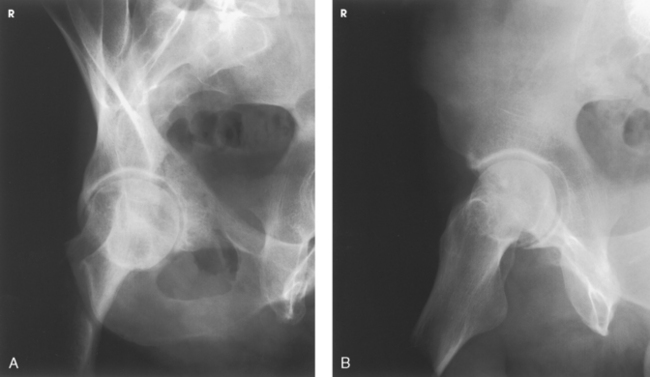

Judet et al.1 described two 45-degree posterior oblique positions that are useful in diagnosing fractures of the acetabulum: the internal oblique position (affected side up) and the external oblique position (affected side down).

The internal oblique position is for a patient with a suspected fracture of the iliopubic column (anterior) and the posterior rim of the acetabulum.

NOTE: Iliopubic column (anterior)—composed of a short segment of the ilium and the pubis; extends up as far as the anterior spine of the ilium and extends from the symphysis pubis and obturator foramen through acetabulum to ASIS.

The external oblique is for a patient with a suspected fracture of the ilioischial column (posterior) and the anterior rim of the acetabulum.

Structures shown: The resulting image shows the acetabular rim (Fig. 7-45).

Fig. 7-45 AP oblique projection, Judet method, right hip. A, LPO. B, RPO. (From Long BW, Rafert JA: Orthopedic radiography, Philadelphia, 1995, Saunders.)

NOTE: Ilioischial column (posterior)—composed of the vertical portion of the ischium and the portion of the ilium immediately above the ischium and extends from the obturator foramen through the posterior aspect of the acetabulum.